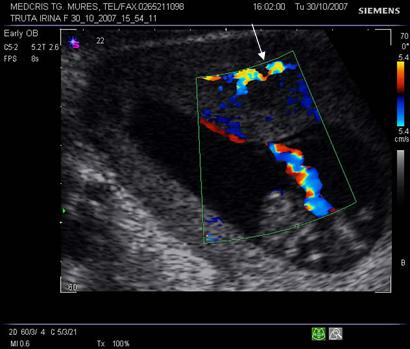

Fig nr. 71. Decolare de pol inferior recenta, la o pacienta cu metroragie si prezenta fluxului sangvin la eco Doppler ( sageata )

Fig. nr. 7 La nivelul hematomului retroplacentar se observa intreruperea circulatiei sangvine uteroplacentare ( sageata). Fluxul sangvin la Doppler, prin cordon ombilical, indica o sarcina in evolutie